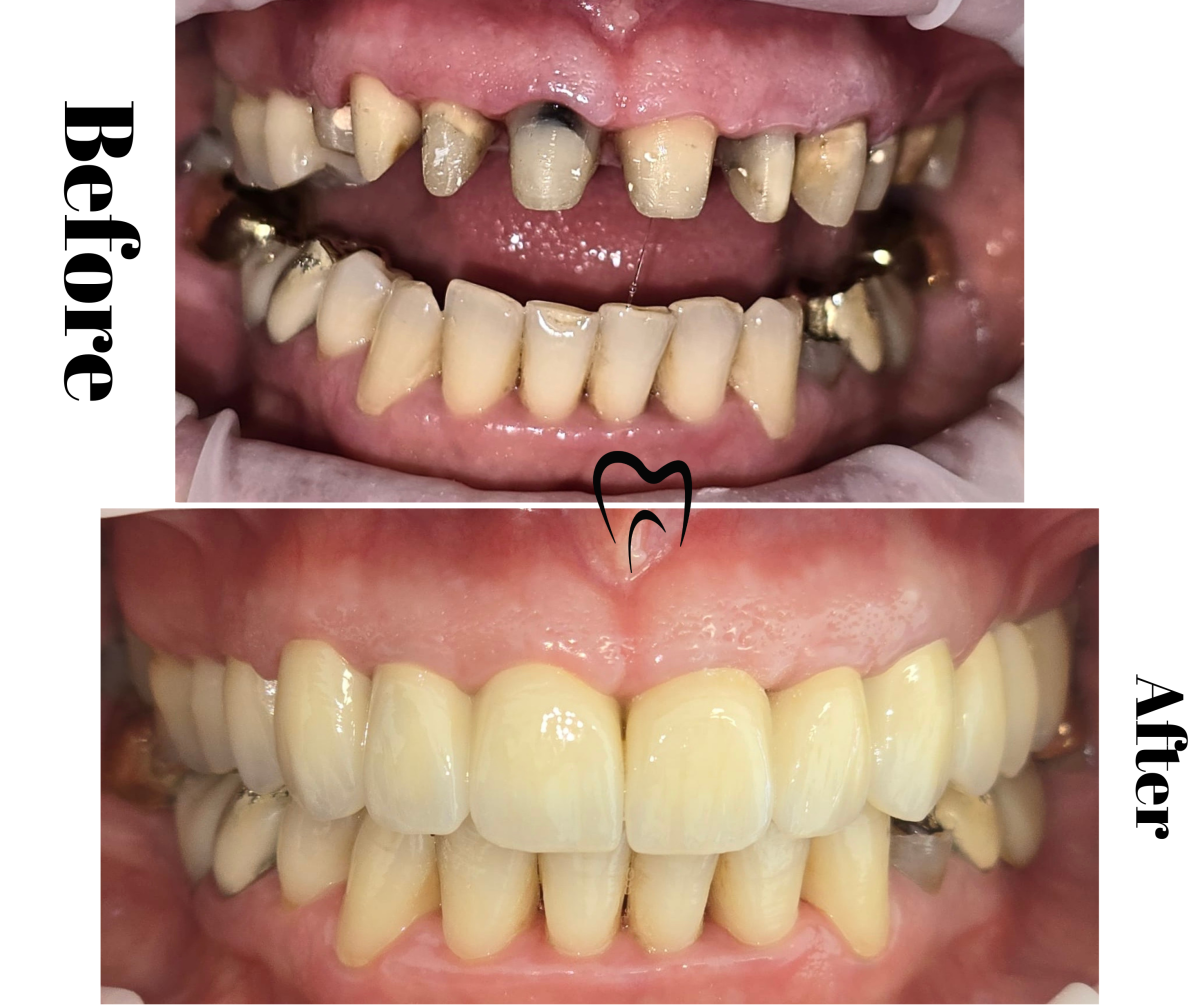

Lucrare superioară metalo-ceramică total fizionomică și proteză acrilică parțială inferioară